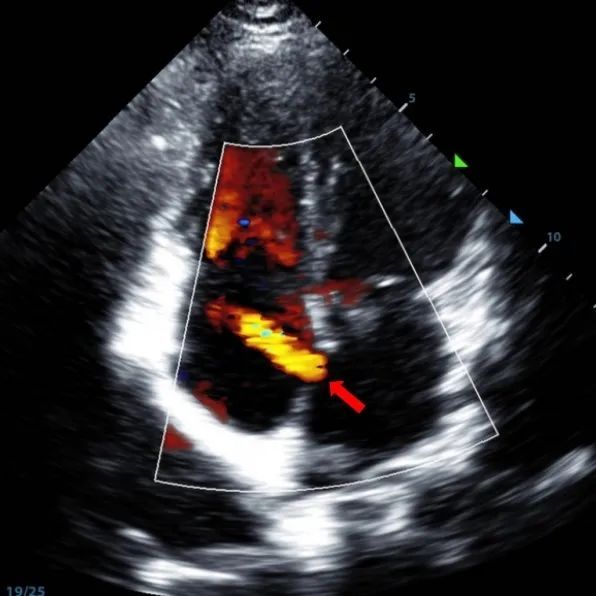

A 9-year-old male with secundum ASD (7.5–7.9 mm) was treated using a MemoSorb BDASD-I 12 mm occluder and 12F delivery system. No complications or comorbidities were noted pre-procedure.

Serial echocardiographic follow-ups showed stable device position and favorable cardiac remodeling. Gradual degradation confirmed the occluder's long-term safety and efficacy.